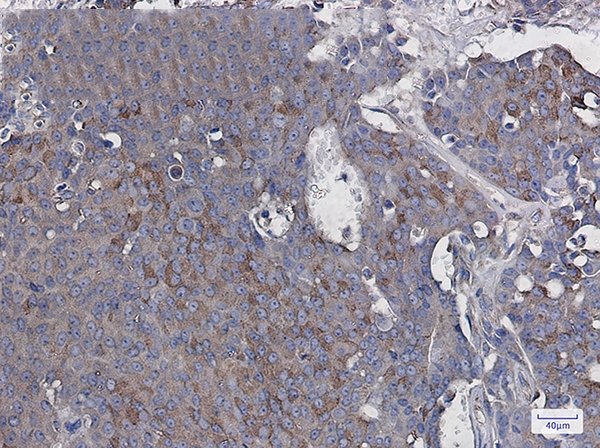

Immunohistochemistry of RAC3 in paraffin-embedded Human breast cancer tissue using RAC3 Rabbit mAb at dilution 1/20